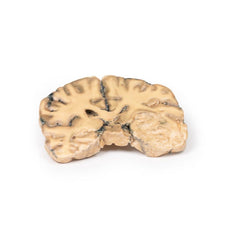

3D Printed Left Cerebral Infarct

The patient was a 51-year old woman who had a cerebro-vascular accident resulting in a left

hemiplegia 2 years prior to death. At necropsy, she had severe generalized atherosclerosis and an old left

ventricular myocardial infarct with an overlying mural thrombus.

A coronal section of the cerebral hemispheres shows irregular cystic cavities in the territory of

distribution of the right middle cerebral artery. The cavities of the infarct have irregular, yellow walls and

show partial collapse. There is compensatory dilatation of the left lateral ventricle. On the posterior aspect,

the arteries below the mammillary bodies were moderately atheromatous, although this is difficult to visualise

macroscopically.

Because of the underlying history of myocardial disease with the presence of the mural

thrombus, it is assumed that her cerebral infarct was probably caused by a thromboembolus.